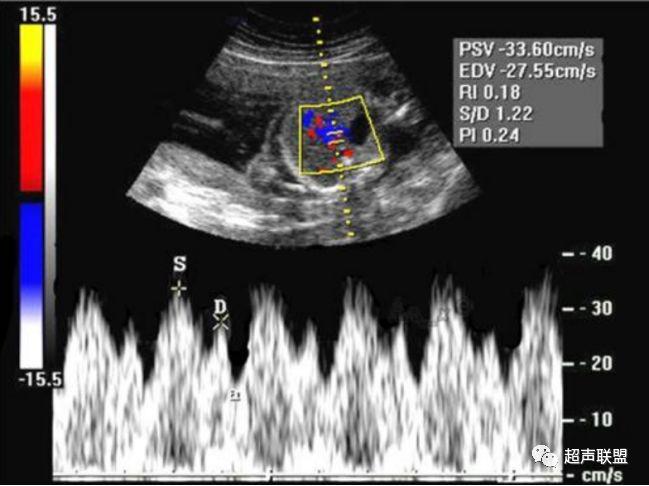

3 胎儿静脉导管

当右心负荷增大,心功能失代偿时,静脉回流受阻,静脉导管a波收缩期流速降落,血流消失甚至倒置。

图5 胎儿宫内正常静脉导管

图6 胎儿宫内缺氧时静脉导管a波反向